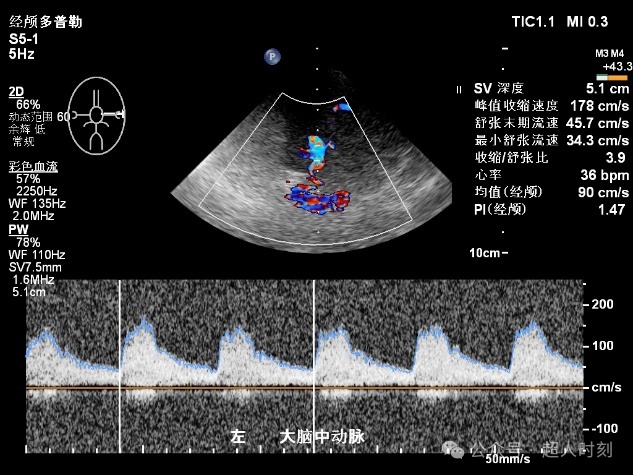

图5f 右大脑前动脉狭窄频谱(VP:263cm/s)